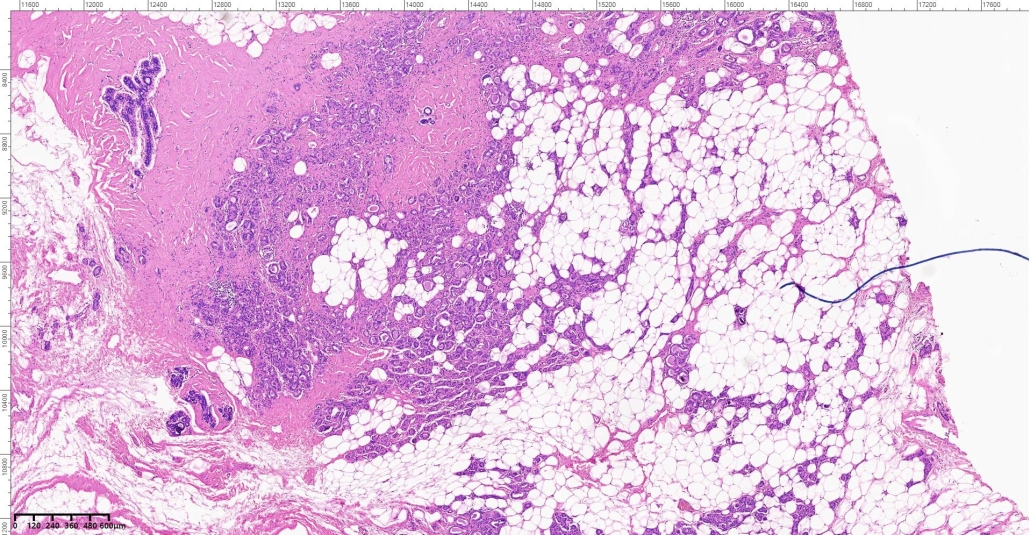

A 46-year-old woman presents with a slowly enlarging, non-tender palpable lump in the upper outer quadrant of the breast. Mammography shows an ill-defined density without calcifications. Local excision is performed.